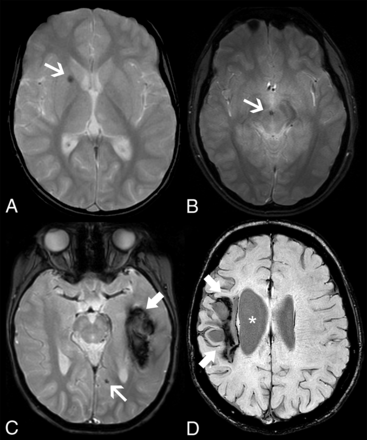

Perivascular enhancing tissue in adenosine deaminase 2 deficiency. Brain MR imaging in patient 1 at 8.5 years of age (A–D) demonstrates a soft tissue component mass in the interpeduncular cistern surrounding the basilar artery and its terminal perforator branches with eccentric vessel wall involvement. The lesion is mildly hyperintense on axial FLAIR (A, arrow), with intense solid enhancement on fat-saturated postgadolinium axial (B) and sagittal (C) T1WI sequences (arrows). DSA (D) reveals normal caliber of the basilar artery and posterior cerebral arteries (arrowheads). Postgadolinium axial (E) and sagittal (F) black-blood T1-weighted images performed at 9.7 years of age, after introduction of anti-TNF treatment, demonstrate a complete resolution of this likely inflammatory perivascular tissue (arrows).

Different from Bulut et al,14 we did not identify any parenchymal area of enhancement after gadolinium injection. However, in one-third of patients, we found another novel feature, which was the presence of irregular, contrast-enhancing tissue in the interpeduncular fossa, crural cistern, and inner auditory canal, surrounding the basilar, posterior cerebral arteries and AICA, respectively. Eccentric vessel wall thickening and enhancement were noted in all patients, more pronounced at the origin of brain stem perforators, leading to progressive arterial stenosis in 1 patient. This pattern slightly differs from the concentric smooth arterial wall involvement typically seen in cerebral vasculitis caused by inflammation-related endothelial or vasa vasorum leakage.20 On the other hand, in 2 patients, this new finding was associated with acute ischemic infarcts in the territory of the posterior perforators, reflecting an active disease phase and suggesting an inflammatory origin. Ac-cordingly, after anti-TNF treatment, there was total tissue regression in all patients and normalization in caliber of the stenosed artery at 1-year follow-up. As in the present series, most skin and bowel biopsy specimens of patients with DADA2 either reveal a PAN-like or a leukocytoclastic type of vasculitis.1,2,10 However, histologic proof of CNS vasculitis was not obtained so far.2 Therefore, the precise mechanism of DADA2-related intracranial vasculopathy remains unknown and awaits further research. Interestingly, most of our patients presented unremarkable angiographic findings. Indeed, abnormalities of intra-cranial vessels have been only occasionally described in DADA2,14,21 probably caused by predominant involvement of medium- and small-sized vessels, frequently beyond the current resolution of lumen-based angiographic studies, including DSA. Accordingly, with the exception of the infarcted tissues, we did not find brain perfusion abnormalities on arterial spin-labeling.